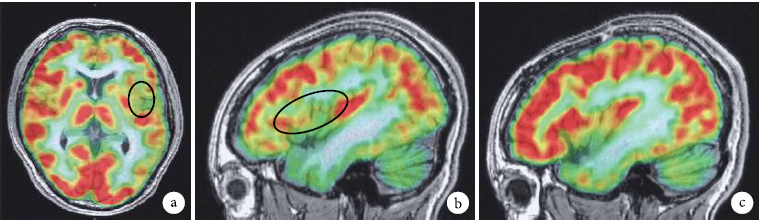

②头颅磁共振(MRI):3.0T薄层扫描提示,与右侧对比,左侧岛叶后部及顶盖脑回较多、较细小,考虑为左侧岛叶后部及顶盖局灶性多小脑回,其余脑组织未见异常信号影(图3)。

1567899612336404.png

图3 MRI薄层扫描3.0T与右侧对比,左侧岛叶后部及顶盖脑回较多、较细小,考虑为左侧岛叶后部及顶盖局灶性多小脑回。a.轴位,b.左侧岛叶岛盖,c.右侧岛叶岛盖